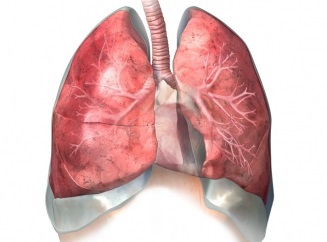

Heg a tüdőben, mint ez azzal fenyeget, akkor

Bármilyen tüdőbetegség, amely már beteg ember, biztos, hogy nyomot hagynak. Még azt jelenti, tüdő specialista meg tudja határozni, hogy hány alkalommal, és a kor, amelyben egy személy betegedett meg tüdőgyulladást vagy egyéb tüdőbetegségek.

Detect heg a tüdő is lehetséges a szokásos „megcsapolt” sztetoszkóp, de pontos diagnózist csak röntgenvizsgálat. Alakult heg (az pulmonologists) a folyamat a „gyógyulás” a fertőzés forrása, melynek helyén kezd növekedni kötőszövet cseréje üresség. Ez az a helyettesítés vezet összevonása az alveolusok (apró részecskék a tüdőszövet). Míg ebben az állapotban, nem tudnak cserélni a szén-dioxid, oxigén. Ezen kívül jelentős probléma az, hogy az alveolusok indul kiürítése és végül is tele váladék, ami a légzésfunkció veszélybe.

Ok hegképződés elvileg bármilyen változás a légutakat. Nem teljesen, illetve nem időben gyógyítható kanyaró, szamárköhögés, tüdőgyulladás, tuberkulózis, hörghurut vezethet kötőszövet képződését. Azonban a hegek nem minden esetben függ a megfázás. Munka szénsavas vagy poros környezetben is eredményezheti pneumokoniózist vagy „Haze” bronchitis. Elég gyakran, hegszövet fejleszt és belélegezve mérgező gyógyszerek. Gyakran okoz sebfelületek amőbás vagy toxoplazmózis. A fejlődési szakaszában a fertőzés „fészek” a tüdő szövetben, és elpusztítja azt. Miután a helyszínen marad heg.

Heg a betegség is jelzi gátolt levegőt. Ebben az esetben, a betegség megnyilvánulhat a bőr kékes az orr alatt. Tovább egyértelmű jele a betegségnek tartják száraz zihálás.

Méretek hegek változhat jelentősen. Sőt, a tünetek közvetlenül függ a mértéke a szerv károsodását. Tételezzük fel, a betegek lefedik az egész testet (diffúz) tüdőfibrózis zavarná erős légszomj, de ez fog megnyilvánulni csak súlyos fiznagruzki.